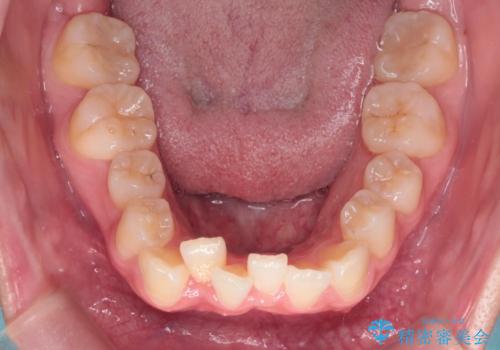

【インビザライン】前歯の凸凹を非抜歯で治療

- 前歯の凸凹を主訴の来院されました。

奥歯を後ろの方に移動させるために矯正用のアンカースクリューを使いながら治療をおこないました。

患者さんの都合により、マウスピースの装着時間が不足したため、途中からワイヤーにて治療を行いました。